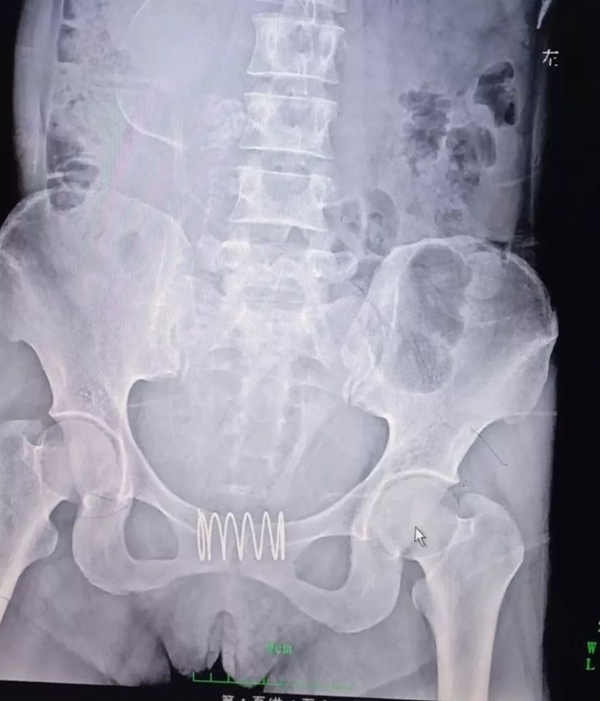

เรื่องราวถูกเปิดเผยขึ้น เมื่อหญิงรายดังกล่าวเกิดตั้งครรภ์ขึ้น จึงเดินทางไปพบแพทย์เพื่อขอความช่วยเหลือให้ช่วยทำแท้งให้แก่เธอ เมื่อช่วงปลายเดือนกรกฎาคม ที่ผ่านมา ทางสูตินรีแพทย์จึงทำการตรวจเช็ก พบว่า เธอมีอายุครรภ์ 5 เดือนแล้ว และที่น่าตกใจไปกว่านั้นคือ เธอมีลวดสปริงคาอยู่ที่บริเวณระหว่างช่องคลอดกับปากมดลูก

ภาพจาก sohu.com

ดร.ฝู จุนหง แพทย์ผู้ชำนาญโรคสตรี เผยว่า ลวดสปริงดังกล่าวที่มีความยาวประมาณ 5 เซนติเมตร แต่ทางแพทย์ไม่สามารถดึงออกมาได้แบบปกติ เนื่องจากมันถูกหุ้มไปด้วยเนื้อเยื่อบริเวณดังกล่าว เพราะติดตรงนั้นเป็นเวลานาน ซึ่งทางคนไข้รับว่า ใส่มันเข้าไปนานประมาณปีครึ่ง แพทย์จึงใช้เครื่องมือตัดออกเป็น 7 ส่วน แล้วค่อย ๆ นำมันออกมาทีละชิ้น โดยการผ่าตัดรักษาครั้งนี้ใช้เวลานาน 40 นาที